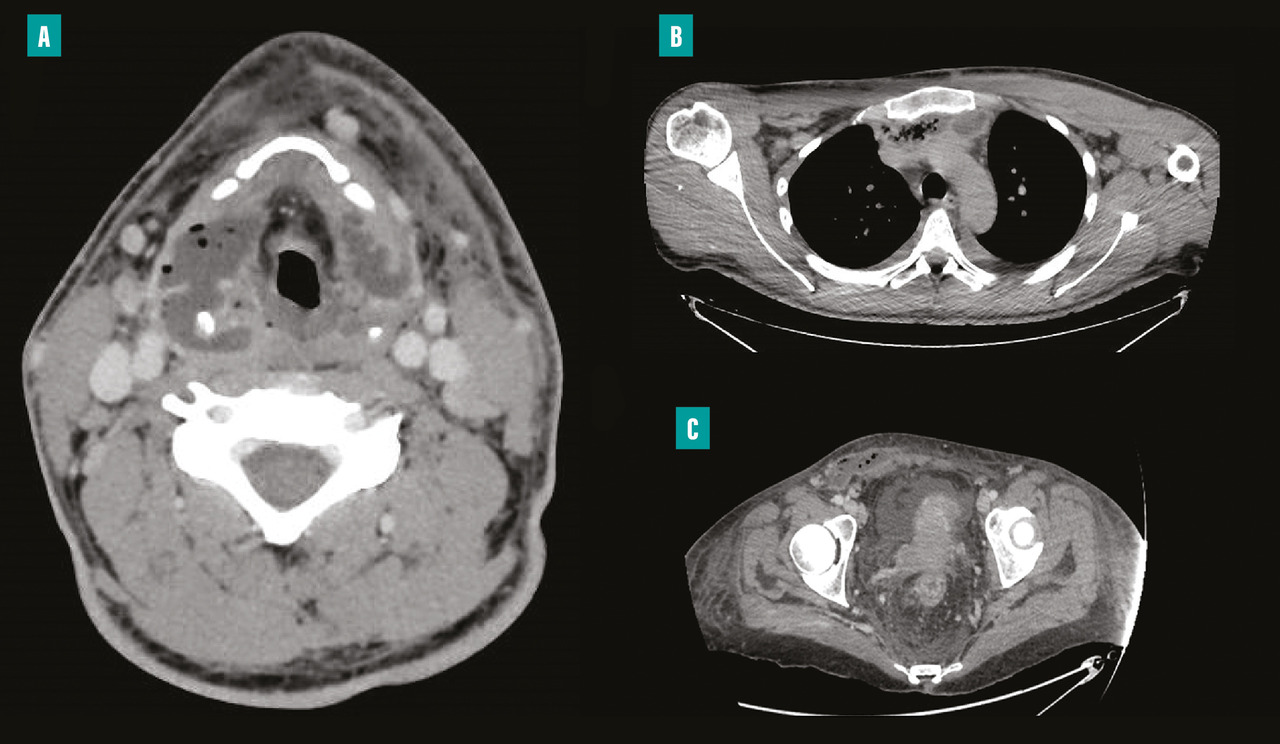

– la présence dans la majorité des cas d’une porte d’entrée à identifier et à traiter dès la phase initiale, avec une importance de l’imagerie pour guider le geste chirurgical (et non pour faire le diagnostic qui reste clinique) [fig. 2 ] ;

– la présence dans la majorité des cas d’une porte d’entrée à identifier et à traiter dès la phase initiale, avec une importance de l’imagerie pour guider le geste chirurgical (et non pour faire le diagnostic qui reste clinique) [

En effet, elles compliquent un foyer infectieux dentaire ou ORL dans respectivement 50 et 20 % des cas, avec une extension médiastinale secondaire objectivée chez 30 % des patients. Cette dernière doit être systématiquement recherchée car elle peut être à l’origine de complications nécessitant dans quelques cas un abord chirurgical thoracique (fig. 2 ).2 Enfin, une thrombose jugulaire n’est pas rare et doit être recherchée sur les examens d’imagerie, en premier lieu un scanner avec injection, afin d’associer un traitement anticoagulant à l’antibiothérapie.

En effet, elles compliquent un foyer infectieux dentaire ou ORL dans respectivement 50 et 20 % des cas, avec une extension médiastinale secondaire objectivée chez 30 % des patients. Cette dernière doit être systématiquement recherchée car elle peut être à l’origine de complications nécessitant dans quelques cas un abord chirurgical thoracique (